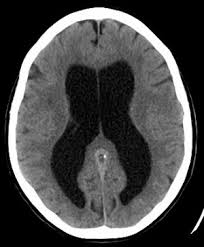

Ct scan without contrast. For a given patient each episode of shunt failure tends to be characterized by similar symptoms 3. Highest incidence of postoperative complications of any neurosurgical procedure.

Bulging fontanelles in infants. Differential diagnosis ventriculoperitoneal shunt problems. Ventriculoperitoneal shunt overdrainage slit ventricle syndrome ventriculoperitoneal shunt infection.

Normal Pressure Hydrocephalus Wikipedia